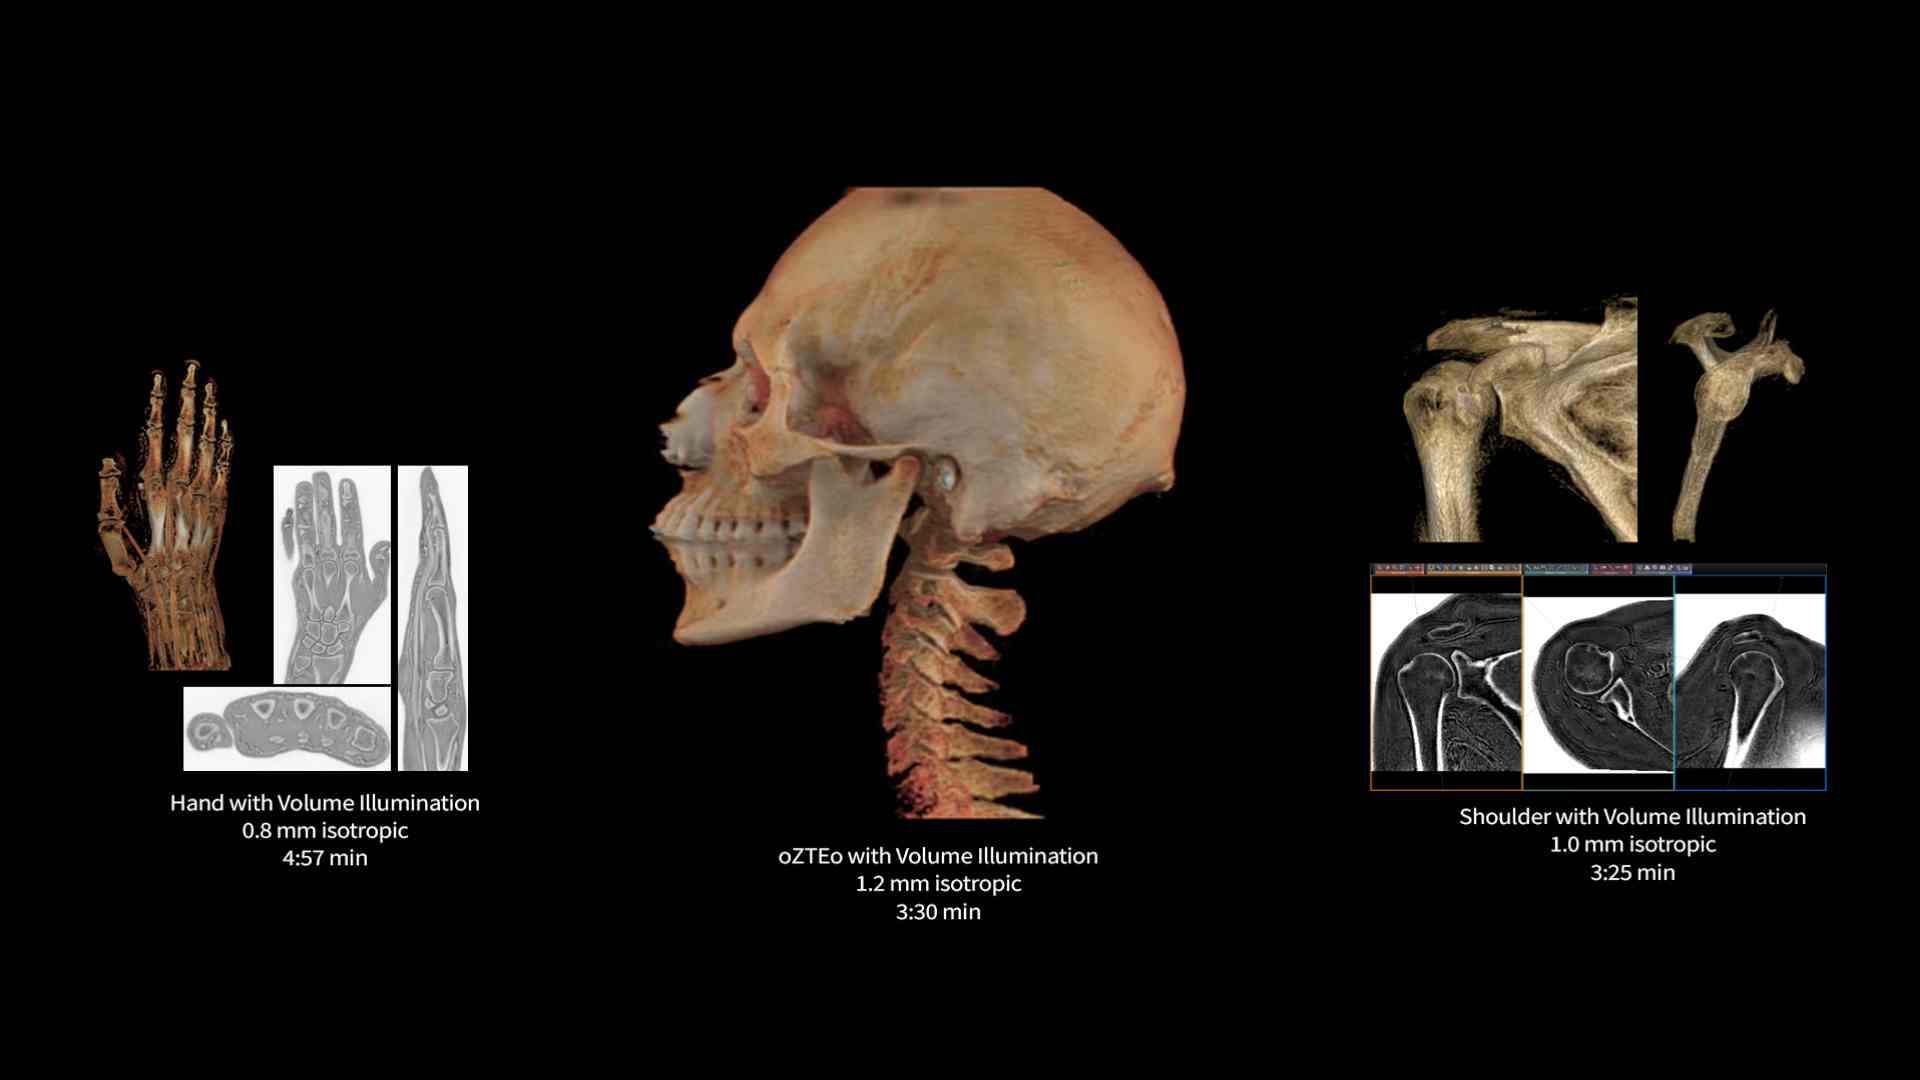

Innovative technology

SuperG 80/200 Gradients, 146 ch TDI Rf Chain, 60 cm performance in a 70 cm bore